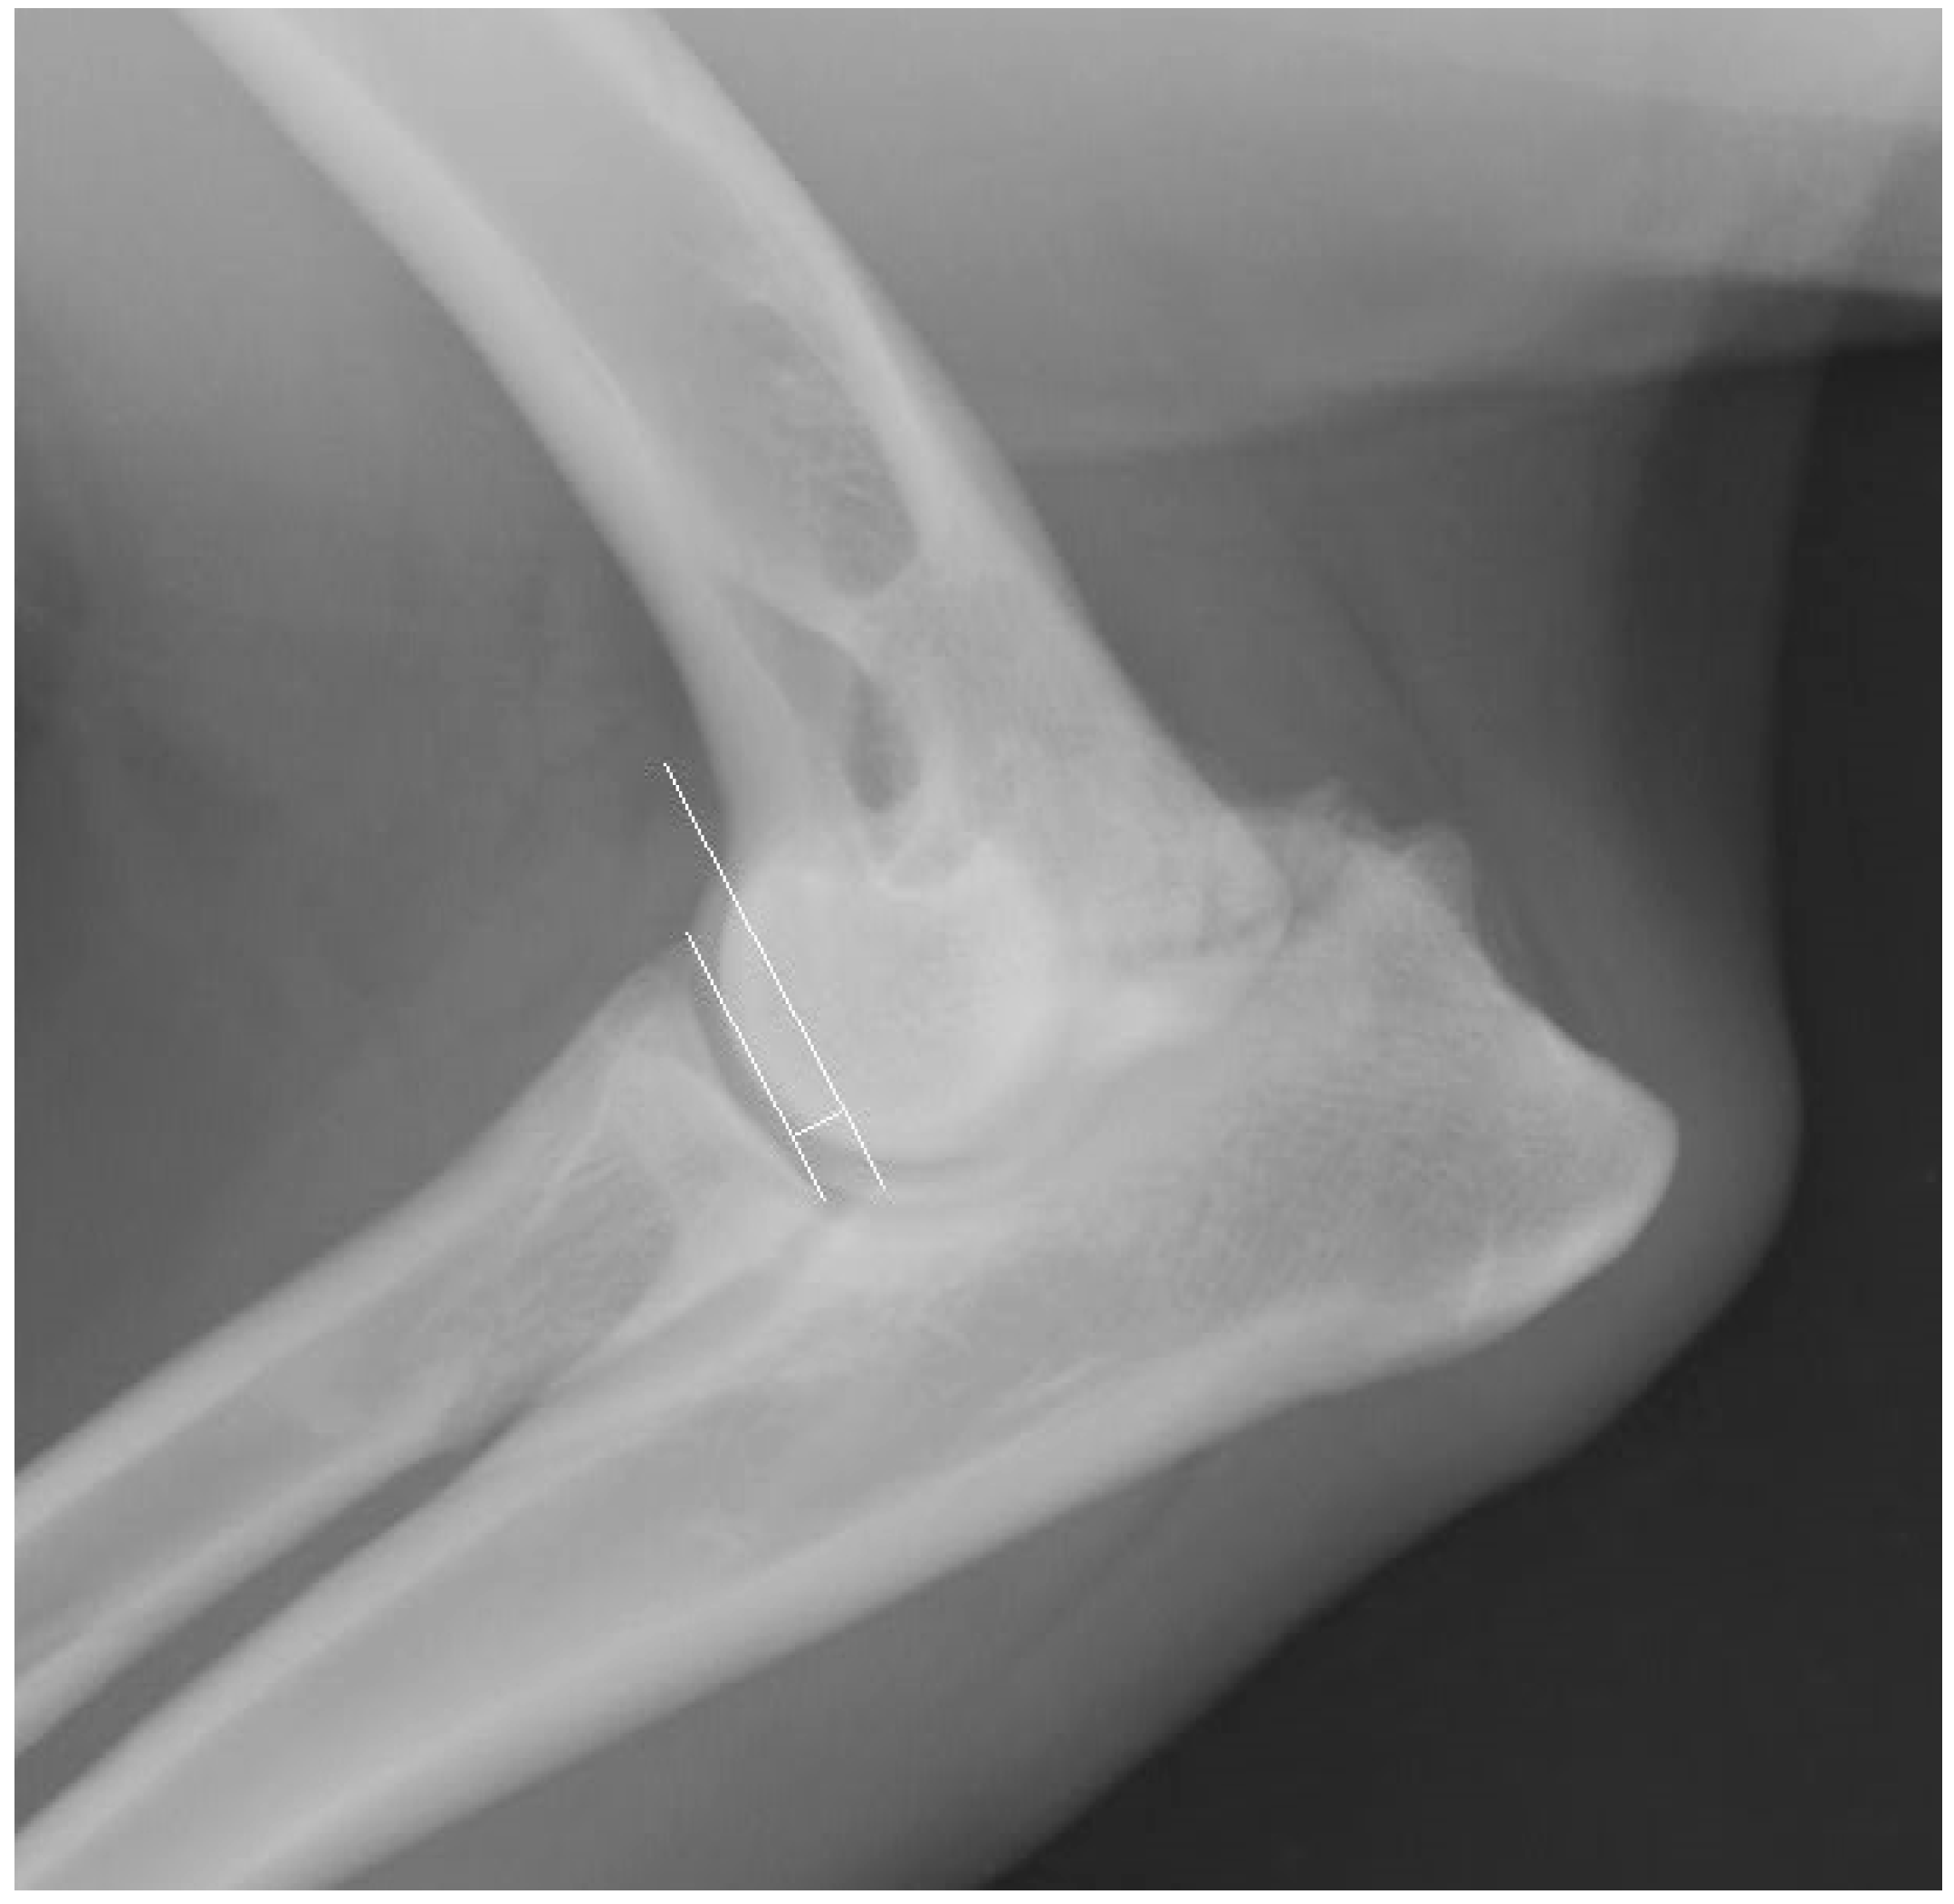

2.5. Measurement Techniques

3.1.1. X-Ray Results for the Elbow Joints

3.2.1. X-Ray Results of the Elbow Joints